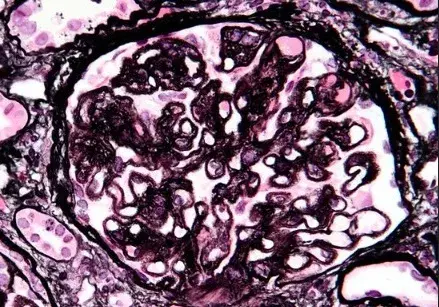

Nefropatia Membranosa: e se o paciente não responder ao tratamento inicial?

Nefropatia Membranosa: e se o paciente não responder ao tratamento inicial?

Neste vídeo, abordamos estratégias para lidar com pacientes com nefropatia membranosa que não respondem ao tratamento inicial. Ele enfatiza a importância da reavaliação constante e do ajuste do regime de tratamento com base nos resultados e no estado do paciente.

Como fazer o tratamento da Nefropatia Membranosa de forma prática!

Como fazer o tratamento da Nefropatia Membranosa de forma prática!